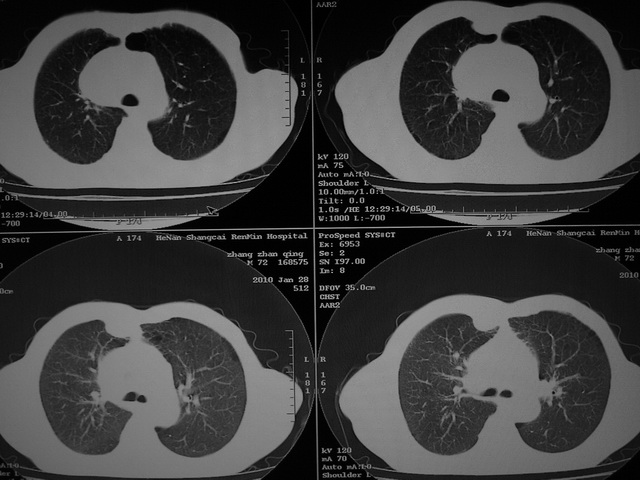

标题: CT24386:M 72岁农民 右侧胸痛6月余,咳嗽,无发热、咯血等 [打印本页]

xx m 72岁农民 右侧胸痛6月余,咳嗽,无发热、咯血等

右下周围型肺癌,并右肺门、纵膈淋巴结、内乳淋巴结转移,右胸膜转移累及前胸壁。鉴别:脓肿、tb、淋巴瘤。病理类型可能为大细胞型。

这个病人有点复杂了,上纵隔像是占位,右肺下叶见壁光整厚壁空洞加液平,像是肺脓肿,中叶病灶牵涉到胸膜及胸壁,形态看像是炎性病变,总之不能除外恶性病变,还是穿刺或增强后再说。

右下周围型肺癌。偏心空洞形成伴感染。

空洞内有液平,支持3楼意见

支持 右肺下叶周围型肺癌并右肺门、纵膈淋巴结、内乳淋巴结转移,右胸膜转移累及前胸壁。